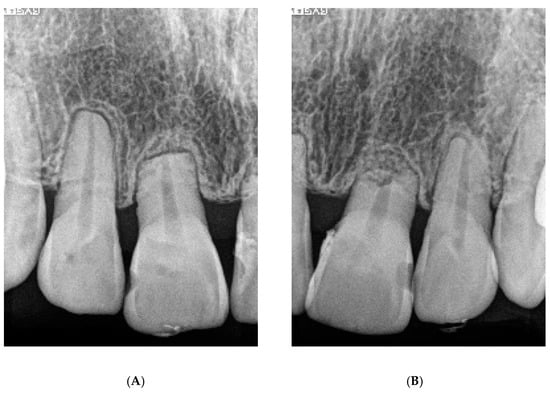

6.1. Diagnosis

6.4. Treatment Progress